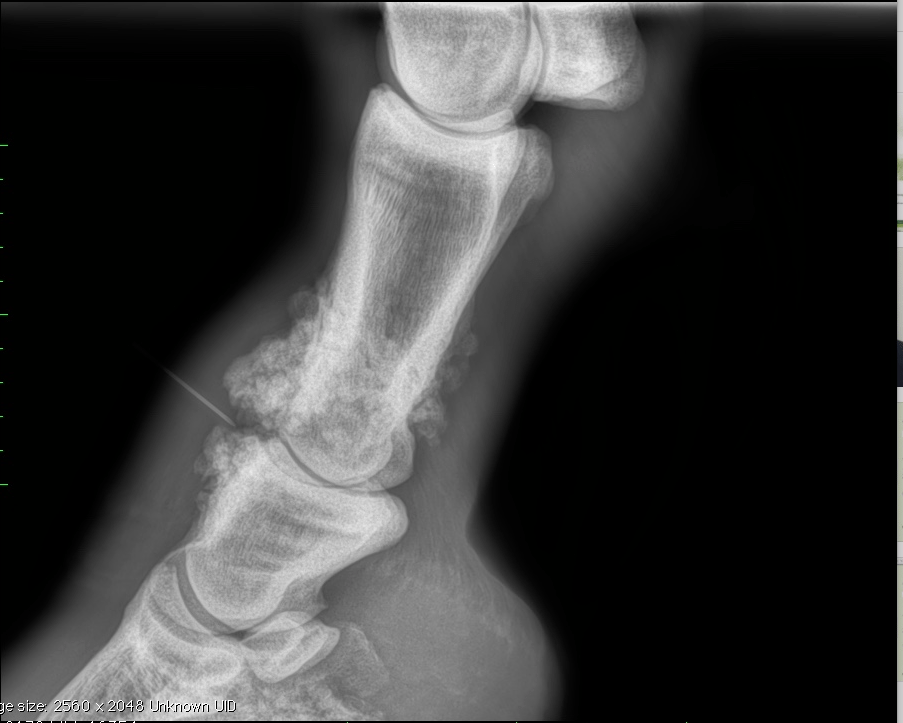

Michael Porter, Equine Veterinarian Hock Arthritis in a Horse What Is Juvenile Arthritis In Horses Important arthritic conditions include traumatic arthritis, osteochondritis dissecans, subchondral cystic lesions, septic (infectious) arthritis, and. Read the latest treatment advice from top vets. But what exactly can you do. Arthritis is inflammation of a joint or joints and can cause reduced performance, pain and lameness. Prevention and treatment for arthritis in horses. Horses can develop arthritis at any age; Arthritis. What Is Juvenile Arthritis In Horses.

Michael Porter, Equine Veterinarian Hock Arthritis in a Horse What Is Juvenile Arthritis In Horses Arthritis is inflammation of a joint or joints and can cause reduced performance, pain and lameness. Dire as that sounds, however, current research is yielding new treatments and investigating management techniques that can help horses work longer and. Read the latest treatment advice from top vets. Osteoarthritis (“oa”) is a common cause of lameness and poor performance in competition horses.. What Is Juvenile Arthritis In Horses.

Michael Porter, Equine Veterinarian Equine Hock Arthritis What Is Juvenile Arthritis In Horses Read the latest treatment advice from top vets. Arthritis is inflammation of a joint or joints and can cause reduced performance, pain and lameness. But what exactly can you do. Arthritis in horses is a degenerative joint disease which involves the joints and cartilages manifested by pain in legs and ultimately leads. Horses can develop arthritis at any age; Arthritis. What Is Juvenile Arthritis In Horses.

(PDF) Fracture, Luxation, and Chronic Septic Arthritis of the What Is Juvenile Arthritis In Horses Arthritis in horses is a chronic degenerative joint disease. Dire as that sounds, however, current research is yielding new treatments and investigating management techniques that can help horses work longer and. Horses can develop arthritis at any age; Osteoarthritis (“oa”) is a common cause of lameness and poor performance in competition horses. Read the latest treatment advice from top vets.. What Is Juvenile Arthritis In Horses.

Juvenile Arthritis DJD Quater Horse What Is Juvenile Arthritis In Horses Horses can develop arthritis at any age; Oa can occur for a variety of reasons. Arthritis in horses is a chronic degenerative joint disease. Dire as that sounds, however, current research is yielding new treatments and investigating management techniques that can help horses work longer and. Read the latest treatment advice from top vets. Arthritis is inflammation of a joint. What Is Juvenile Arthritis In Horses.